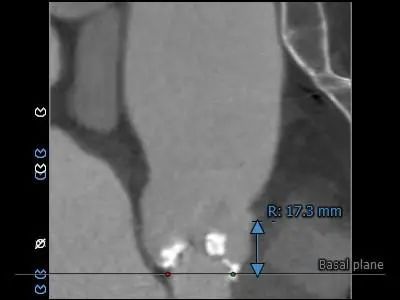

2021年12月4日,郑州市第七人民医院赵育洁主任、张申伟主任团队成功完成TaurusElite®可回收经导管主动脉瓣系统首例植入。此病例十分典型,Type 0型二叶式主动脉瓣,重度钙化主要沿两窦瓣叶边缘连续分布,瓣叶增厚,窦内少量钙化向窦底延伸至瓣环水平,瓣环水平夹角54接近横位心,升主动脉严重扭曲。术后瓣膜工作正常稳定,未出现冠脉阻挡和瓣周漏等情况,血流动力学均得到有效改善,为患者带来更长久生存期受益和更高生活质量。

患者:女性,71岁,以间断胸闷气短4年为主诉入院,术前诊断:1.冠心病2.高血压病2级3.主动脉瓣重度狭窄二尖瓣重度关闭不全4.心律失常,三度房室传导阻滞。术前峰值跨瓣压差 120mmHg,瓣上速度 4.5m/s,瓣口面积0.8cm²。

1.Type 0 型二叶瓣,瓣叶增厚,双侧瓣叶边缘连续条状钙化,瓣膜锚定难度适中,瓣膜植入受两侧钙化挤压存在移位风险及瓣周漏风险。

3.接近横位心,升主动脉扭曲,弓顶部角度略锐,宽度适宜,预计输送器可顺利过弓,输送器跨瓣难度增高,必要时Snare辅助。

主动脉根部测量

瓣上测量